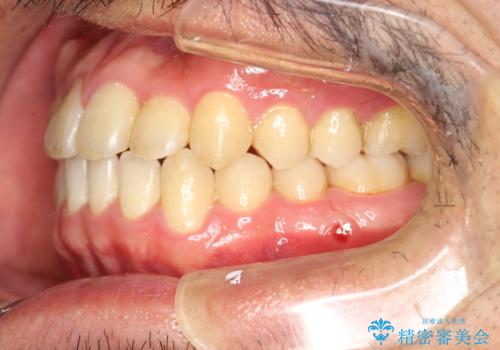

前歯が反対にかんでいる インビザラインとワイヤーを組み合わせた矯正治療

- 1年1ヶ月

マウスピースのみでの治療も可能でしたが、治療期間がもう少し延長していた可能性があります。